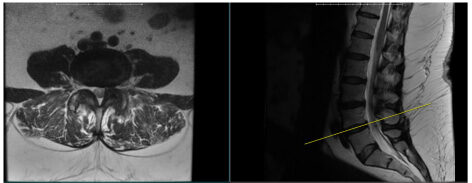

MRI showing compression of the nerves at the L4/5 level in same patient as x-rays. Notice on the MRI the step-off in the spine is gone. When the patient stands, the nerve compression gets worse because the spine slips forward.